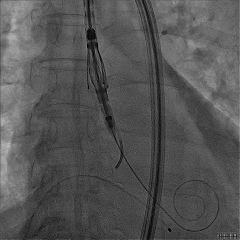

建立右侧股静脉入路,在食道超声引导下进行房间隔穿刺,获得穿刺高度4.1cm,交换Super Stiff超硬导丝至左上肺静脉,使用血管鞘扩张股静脉后,沿超硬导丝送入可操控导引导管(SGC)至左房,将第一枚二尖瓣夹输送系统(CDS-XTR)送入左心房。送入夹子过程中为避免碰到左房组织完成Straddle“骑跨”,顺利完成Straddle并将夹子打弯至二尖瓣环水平。接下来为避免发生缠绕在1区进行轨迹测试,使夹子的运动轨迹指向心尖。在心房侧打开夹臂,调整夹臂方向指向12点-6点方位,与二尖瓣对合缘垂直。完成调整后将夹子移动至3区位置,将二尖瓣夹关紧后缓慢送入左心室。在左室打开夹子重新确认Orientation。准确成功捕捞3区前叶脱垂及反流区域,确认瓣叶瓣尖稳定插入夹臂后,Gripper Down,观察到明显Bouncing后,关紧夹臂予以夹合,夹子内侧反流消失,夹子外侧还有残余脱垂及中量反流。考虑瓣叶长度11mm以上,瓣口面积足够,决定在外侧Side by Side再植入一枚XTR,植入两枚XTR后活动稳固,反流降至Trace。术后肺静脉逆流消失,二尖瓣平均跨瓣压差2mmHg。

送入第2枚XTR在左房调整轨迹及Orientation

进入瓣下重新确认Orientation及位置

捕捞瓣叶,确定瓣叶瓣尖稳定插入夹臂后,Gripper Down

关紧后,前后叶受限明显

3D Enface下组织桥稳定无反流

夹子释放后,反流基本消失

LVOT切面可见主瓣二尖瓣术后反流基本消失

植入两枚夹子后二尖瓣平均跨瓣压差2mmHg